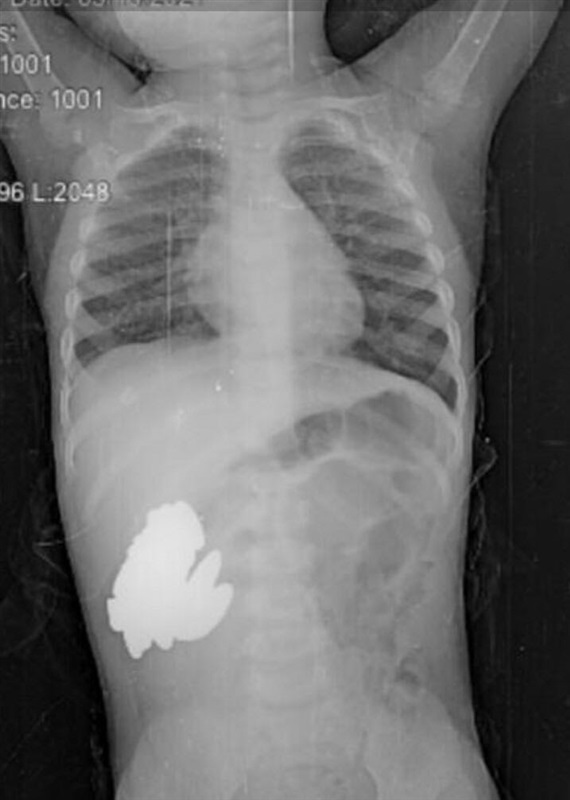

نجح الفريق الطبي في قسم جراحة الأطفال بمستشفى جامعة الزقازيق من إنقاذ طفله في عمر العام والنصف حضرت بها والدتها للقسم في حالة لا يرثى لها تشكو من معاناتها بالقئ والآم في البطن منذ ما يقرب من الأسبوع  ليهرع بها الأطباء، وبعمل عدة اشعات تبين وجود جسم غريب داخل البطن فقرروا خضوعها لعملية جراحيه عاجلة.

وجاء الفريق الطبي من فريق عمل الحوادث من جراحة الأطفال برئاسة الدكتور أحمد عزت رئيس القسم وفريق من قسم التخدير، ليتفاجئوا بوجود ما يقرب من 30 قطعة معدنية داخل أحشائها عباره عن صواميل ومغناطيس وهي ما تسببت في حالة القئ والإعياء الشديد التي عانت منهم الطفلة على مدار أيام  وتم استخراج القطع بنجاح، فيما أفادت الأم بأن الطفلة تلهو في الشارع بالقرب من إحدى الورش وربما ابتلعت هذه القطع أثناء ذلك.